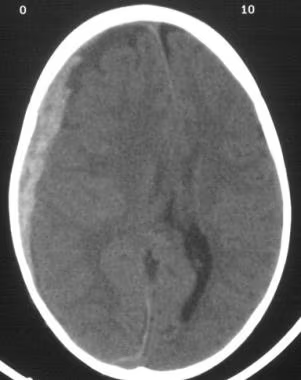

- CCT nativ (Blutung, Ödem, Fraktur, Mittellinienshift)

- Epiduralhämatom: A. meningea media, freies Intervall, CCT: bikonvex → sofortige Trepanation

- Subduralhämatom: Brückenvenen, akut (Stunden) oder chronisch (Wochen), CCT: sichelförmig → Trepanation bei Raumforderung

- ICB: Hypertonie, Antikoagulation, CCT: hyperdens intrazerebral → intensivmedizinisch, Gerinnung korrigieren